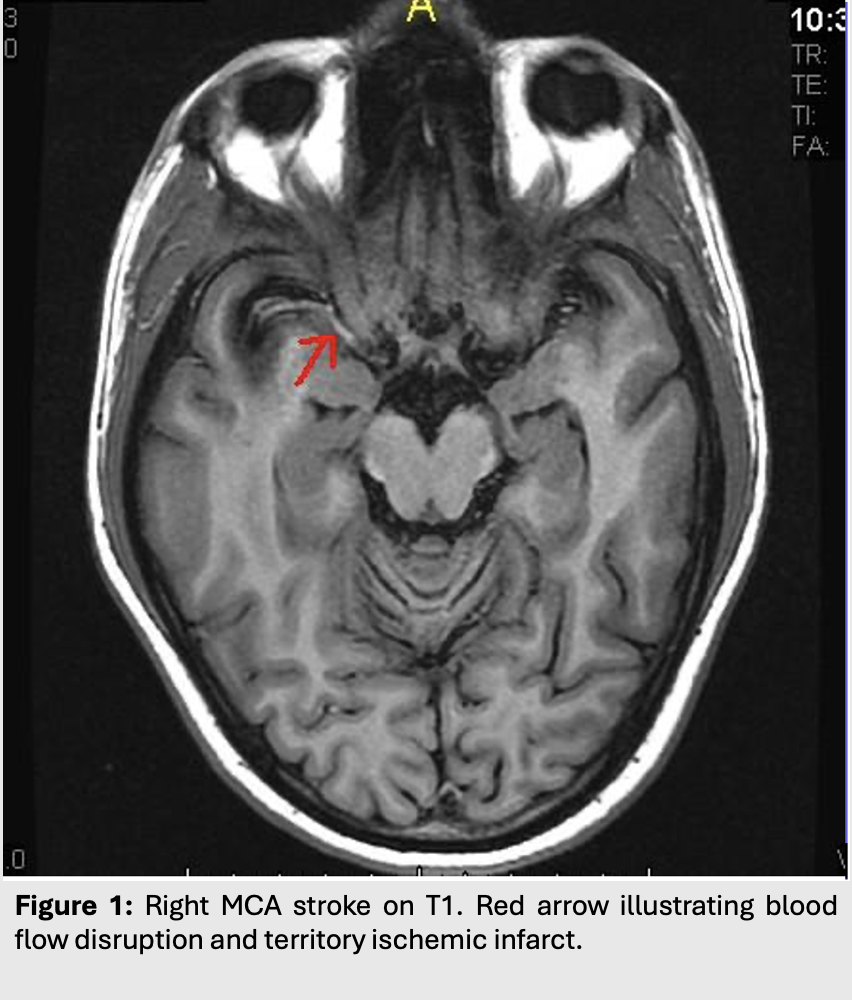

Figure 1: Right MCA stroke on T1. Red arrow illustrating blood flow disruption and territory ischemic infarct.

This type of edema is most commonly seen in strokes or ischemic syndromes.

Cytotoxic edema occurs in situations where the blood brain barrier is intact.

Edema results from shifts of fluid into cells, most often as a result of membrane pump failures following cell death in the case of ischemia or infarcts.

This leads to edema with restriction of water diffusion. As such, cytotoxic edema will appear hyperintense on both T2/FLAIR and on DWI.